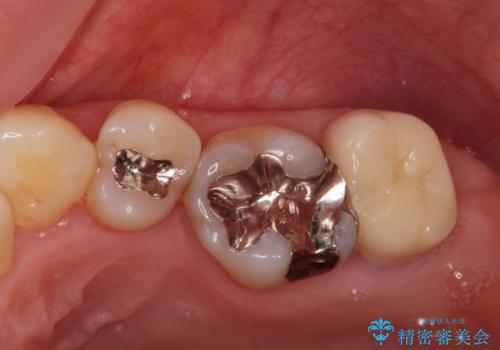

被せ物、古い材料を徹底的に除去し、ラバーダム防湿にて無菌的処置を行い、セラミックの被せ物で治療を行いました。

治療が終了してからも定期的にレントゲンをとり経過観察を行いました。

病巣は現在縮小しておりまた白い被せ物が入り患者様に満足してもらえました。